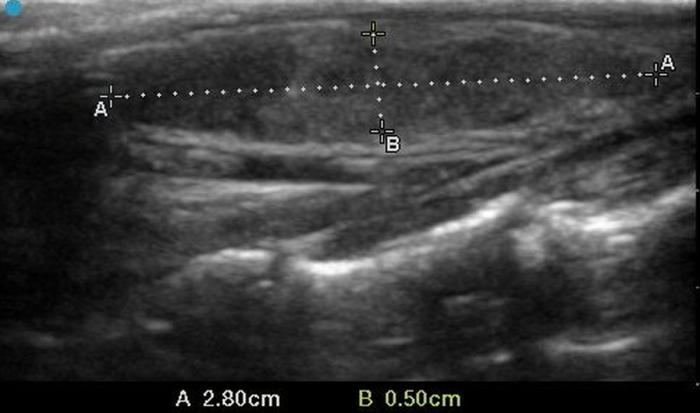

El uso de estructuras vasculares adyacentes como referencias anatómicas ha sido una estrategia útil en ecografía veterinaria para estandarizar las mediciones de órganos pequeños como la glándula tiroides. En este contexto, Bandula Kumara et al. (2019) propusieron la medición de la relación entre el diámetro tiroideo (TD) y el diámetro de la arteria carótida común (CCA) como una forma práctica de evaluar el tamaño de la glándula en perros clínicamente normales (Figura 5A-B).

Los autores realizaron un estudio en el que midieron el diámetro anteroposterior de los lóbulos tiroideos y el diámetro externo de la CCA en cortes transversales obtenidos a nivel del cuello medio. Encontraron que esta relación se mantiene relativamente constante entre razas y tamaños corporales, sugiriendo que puede ser utilizada como parámetro de referencia ecográfica. Específicamente, en perros adultos sanos, la relación TD/CCA fue de 1.74 ± 0.40 (rango 1.11–2.43)6. Si los valores se encuentran por debajo del rango normal pueden ser considerados potencialmente indicativos de hipoplasia tiroidea o atrofia glandular.

Una ventaja de esta relación es que la arteria carótida común es fácilmente identificable ecográficamente, presenta un diámetro estable y poco variable en condiciones fisiológicas, y se ubica en estrecha proximidad con la glándula tiroides. Esto la convierte en una excelente estructura de referencia para normalizar mediciones entre individuos de diferente tamaño corporal, permitiendo evaluaciones objetivas en poblaciones mixtas de perros de compañía.

Además, este índice podría tener aplicación clínica en el seguimiento de animales con enfermedad tiroidea subclínica o en tratamiento, ya que permite detectar cambios discretos en el volumen glandular con buena reproducibilidad interobservador. Aunque su utilidad clínica requiere aún validación en animales con patología confirmada, representa una herramienta complementaria valiosa dentro del enfoque ecográfico sistemático de la glándula tiroides en pequeños animales.